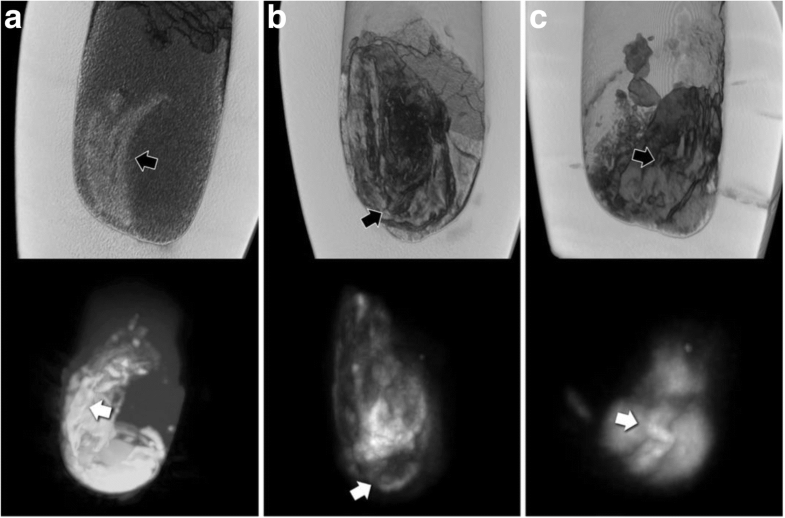

CT reconstructions (top) and correlative maximum intensity projections of MRI scans (bottom) of the three canopic jars with solid contents (a, inventory number 607; b, inventory number 617; c, inventory number 622-1). Black arrows (on CT) and white arrows (on MRI) indicate structures of organ-fragment-like morphology, probably intestine

The structures identified in the contents of canopic jar 607 would be far more compatible with a small organ fragment (potentially intestine) rather than an entire mummified organ. Strikingly, the corresponding MRI images can be viewed as highly compatible with the information provided by the CT scans. The observed pronounced variations in signal intensity coincide very well with the aforementioned structures of distinct morphology, identified with the CT scans, in particular for jar 607. Reasonably, it can be proposed that the image contrast observed in all three MRI scans was caused by organic mummification agents, which were absorbed by the mummified biological tissues. The fact that the outer border of these structures produced the most intense signal where most of the embalming substances would likely accumulate supports this interpretation. Another possible interpretation, however, could be that very thin gaps have formed between the dense structures identifiable on the CT scans and the surrounding material, which may have led to susceptibility artefacts on MRI.

As one would expect, CT in general provided far superior detail over MRI, essentially due to the higher spatial resolution, but further research will be necessary to determine the full capacity of MRI for this application. The fact that contrasts on MRI and CT complement each other for the examination of ancient Egyptian canopic jars is an advantageous result, encouraging further research.